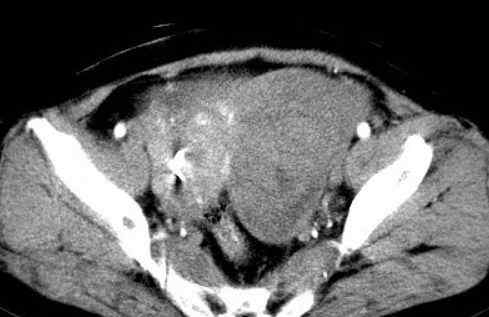

病史:女,51岁。没有任何不适,家人以为他们胖了。

病理结果:浆膜下子宫肌瘤(阔韧带肌瘤)

术中发现与左侧子宫壁、阔韧带关系密切,与左侧卵巢有粘连。

影像表现:

2.CT检查

大部分都是偶然发现的。子宫呈骨状,或子宫局部增厚,与子宫肌密度一致。变性时密度低,钙化时密度高。增强程度弱于子宫肌。

此例为巨大阔韧带肌瘤,易于诊断。